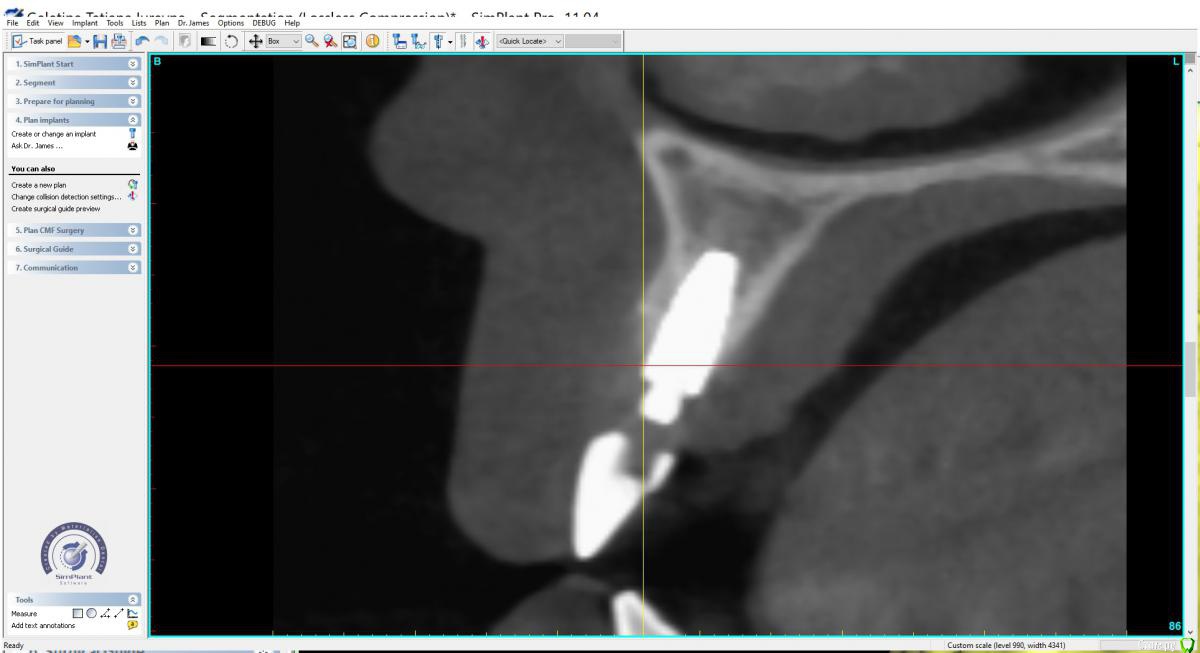

Irouil Опубликовано 1 сентября, 2019 Поделиться Опубликовано 1 сентября, 2019 Тут бы рентген смотреть Ссылка на комментарий

x4ex Опубликовано 1 сентября, 2019 Автор Поделиться Опубликовано 1 сентября, 2019 Тут бы рентген смотреть Ссылка на комментарий

Дмитрий М Опубликовано 3 сентября, 2019 Поделиться Опубликовано 3 сентября, 2019 12 - имплантат.так по снимку 12 - свой зуб! это резорбция у шейки или недозаглубили? Ссылка на комментарий

Irouil Опубликовано 4 сентября, 2019 Поделиться Опубликовано 4 сентября, 2019 (изменено) Я думаю, что если на такой глубине протезировать винт и рассчитывать на эстетику, то апроксимально Вам нужны твёрдые ткани на его плечах. Я бы попробовал туда подсадить два фрагмента бугра (вероятно - с эмд) и укрыл бы все надкостнично-соединительнотканным лоскутом с неба. Через 4 месяца раскрывать винт и идти на жесткое переключение платформы с подсадкой стт с бугра. Изменено 4 сентября, 2019 пользователем Irouil Ссылка на комментарий

Dman Опубликовано 4 сентября, 2019 Поделиться Опубликовано 4 сентября, 2019 так по снимку 12 - свой зуб! 358.jpg это резорбция у шейки или недозаглубили? по всем снимкам 12- имплант, вы точно врач? опишите пожалуйста, каким именно? ну видно же, что на примерке ишемия, значит абатмент выталкивает мягкие ткани вестибулярно и коронально. Если делать пластику то трансплантат будет находиться и расти в том же направлении. Значит нужно сделать более вогнутый абатмент с переходом в коронку намного ниже, там, куда мы хотим сместить зенит. а для чего глушить? чтобы получить больше мягких тканей, потом сместить их вестибулярно, и получить необходимую высоту. Также будет возможность провести на раскрытии еще пластику и добавить ещею 1 Ссылка на комментарий